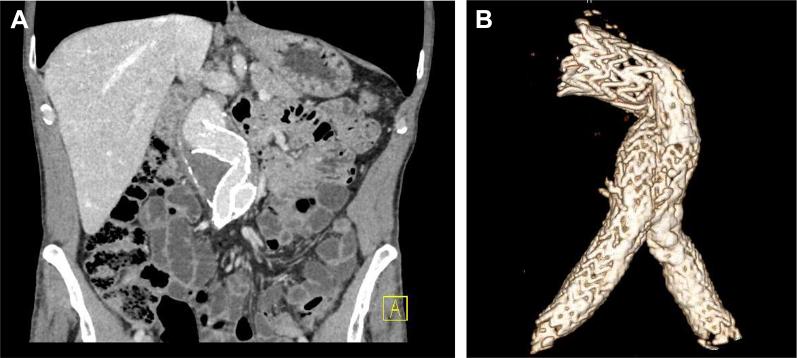

Widespread adoption of endovascular aneurysm repair has led to increased incidence of late complications, such as endograft migration. Treatment options have to be tailored to the patient's health, quality of proximal aorta, and extent of migration. Complete or partial endograft removal is associated with significant morbidity and mortality. We describe a case in which open repair with endograft preservation was employed, with the additional benefit of a sutured proximal anastomosis.

血管内动脉瘤修复术的广泛应用导致了晚期并发症(如移植物移位)的发生率增加。治疗方案必须根据患者的健康状况、近端主动脉质量和移位程度进行调整。完全或部分移除移植物会带来显著的发病率和死亡率。我们描述了一例采用保留移植物的开放修复术的病例,其额外的益处是近端吻合口采用了缝合的方式。